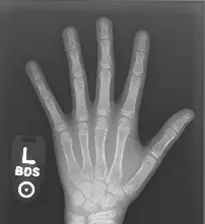

Bone age Assessment system

- طوّرتُ نظام تعلّم آلة للتنبؤ بالعمر العظمي - إخفاء الصور والكشف عن الكائنات - مطابقة القوالب - استخدمتُ Python وOpenCV - استخرجتُ الميزات ودرّبتُ النموذج - يُبرز خبرتي في مجال رؤية الحاسوب